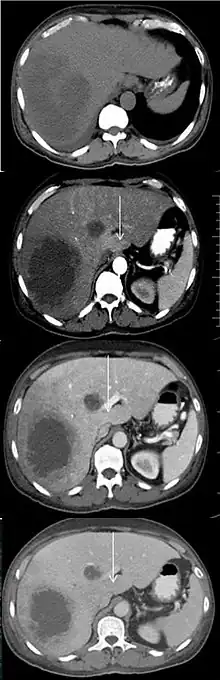

An abscess and a THAD (white arrow) on a contrast CT in native, arterial, portal and delayed phase.[1]

Transient hepatic attenuation differences (THAD) are areas of enhancement during the arterial phase of contrast CT of the liver. THAD is thought to be a physiological phenomenon resulting from regional variation in the blood supply by the portal vein and/or the hepatic artery. THAD may in some cases be associated with liver tumors such as a hepatocellular carcinoma.[2]